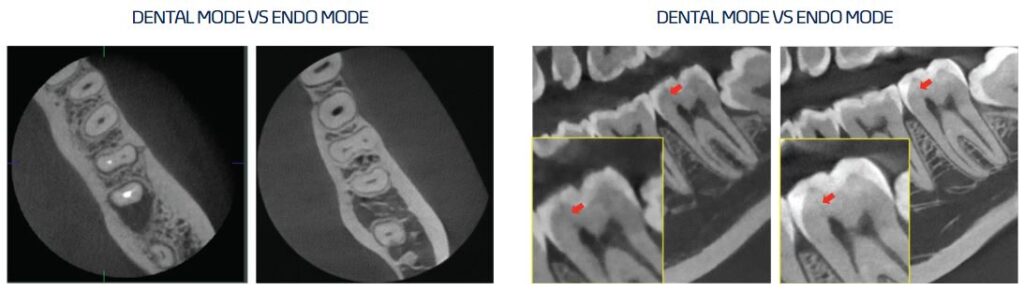

Endo Mode with High Resolution

With its 4cm x 4cm volume mode and 49.5 micron voxel size, the Endo mode will optimise treatment of highly-focused regions of interest. It is ideal for endodontic use because the dentist is able to achieve an extraordinary image in a high-resolution voxel size.

- Highest Resolution Endo solution with 0.05mm Voxel Size (4×4 Endo mode)